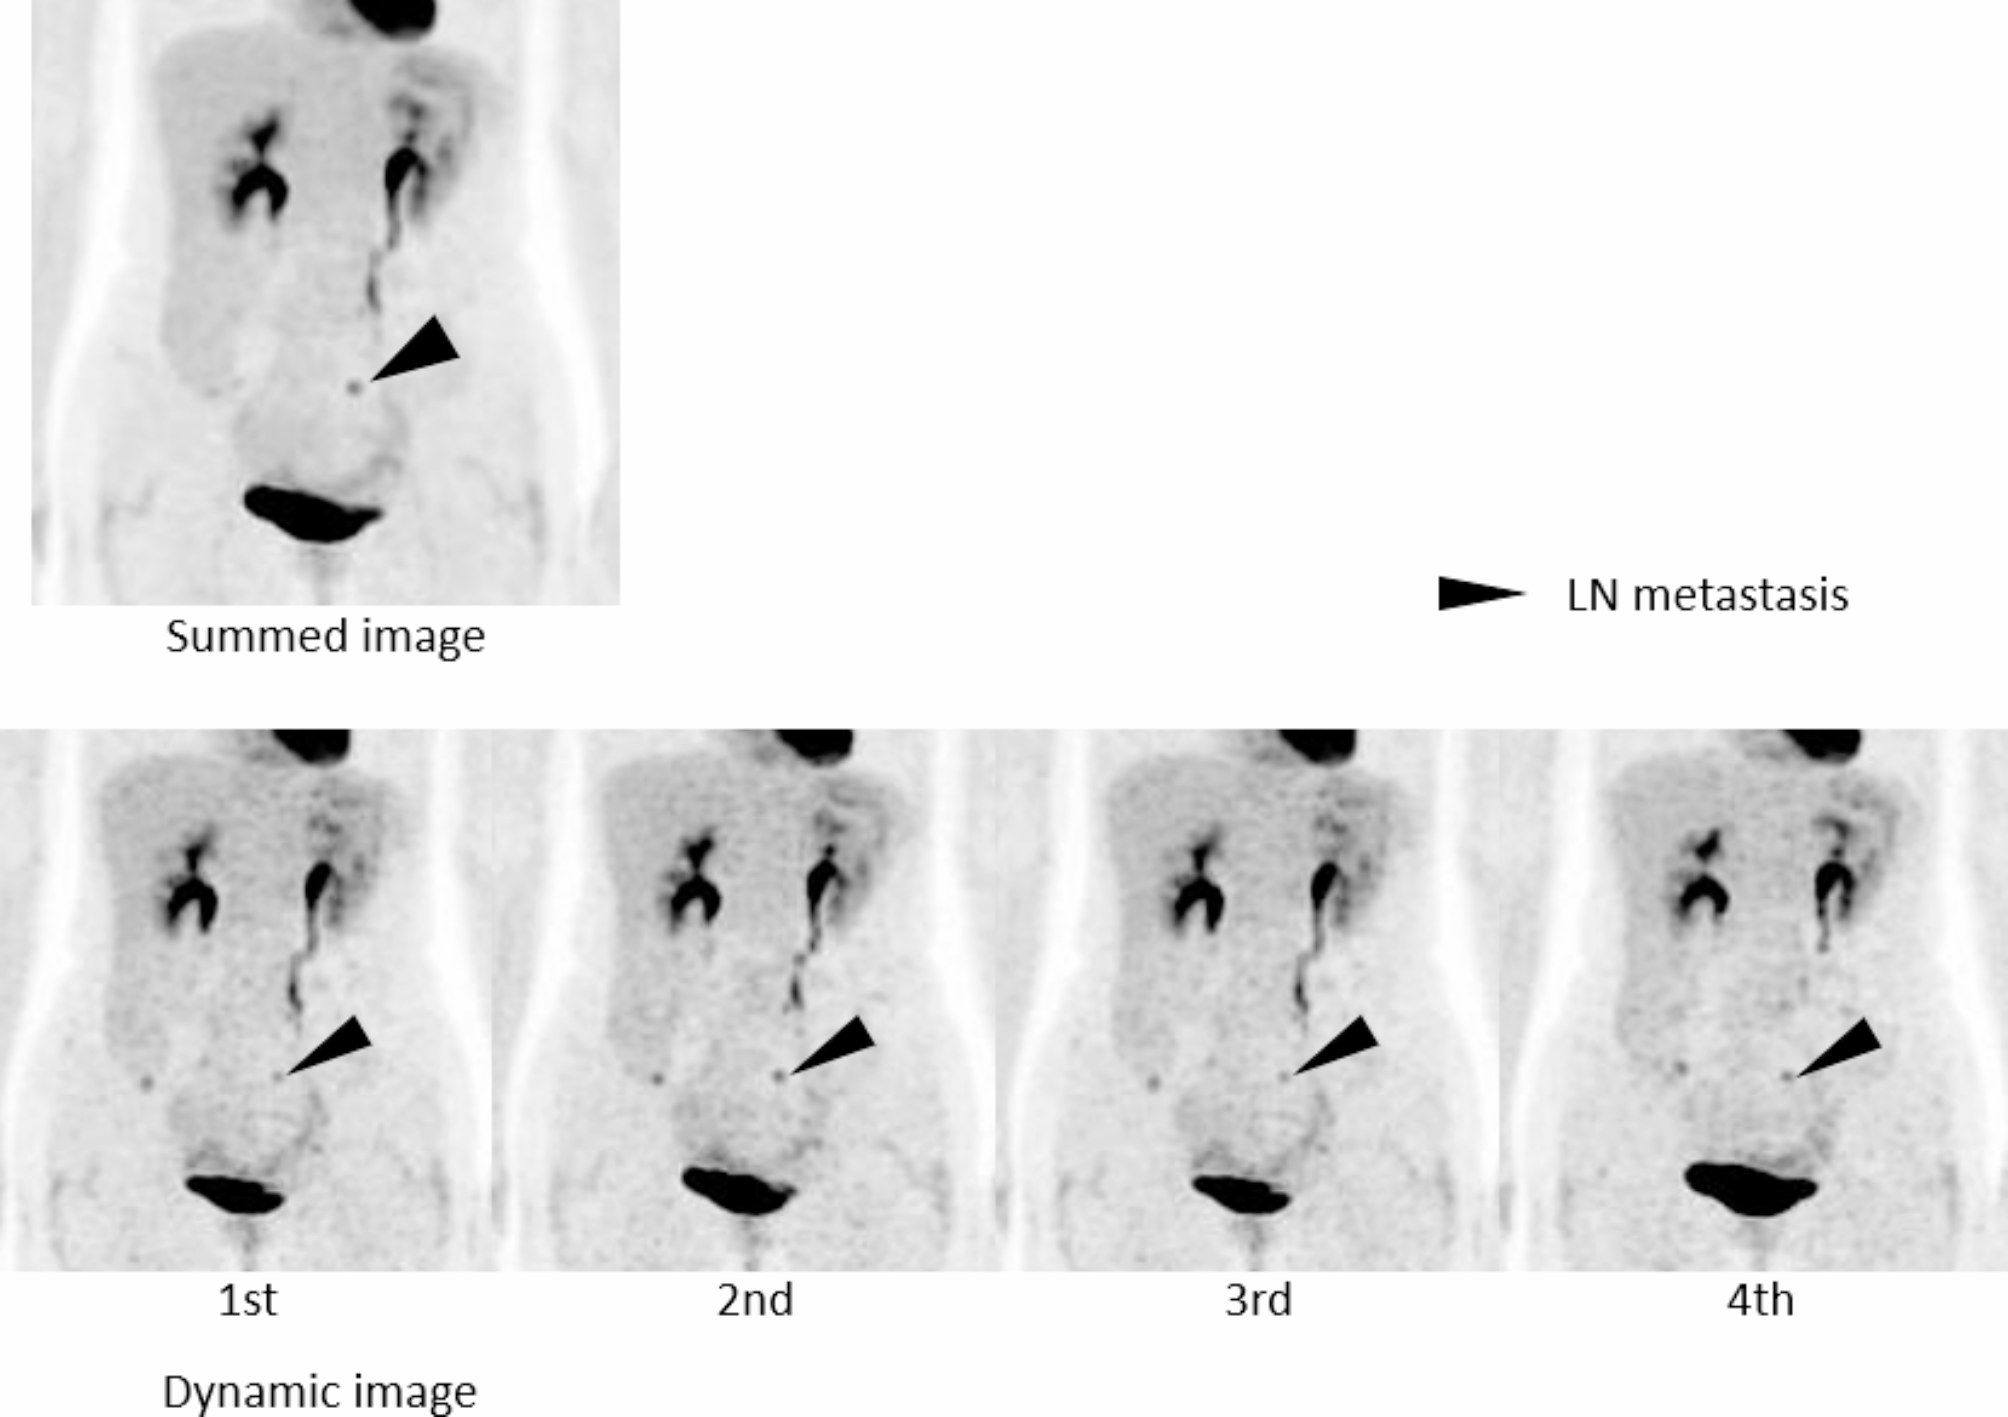

Fig. 4

Summed image and four serial whole-body dynamic PET images (1st − 4th, 3 min each) of a patient with recurrent ovarian cancer. The summed image shows one focal hot (arrowheads). There is no change in the morphology of the uptake in the dynamic four-phase images, suggesting pathological uptake. This one was clinically diagnosed as lymph node metastasis.